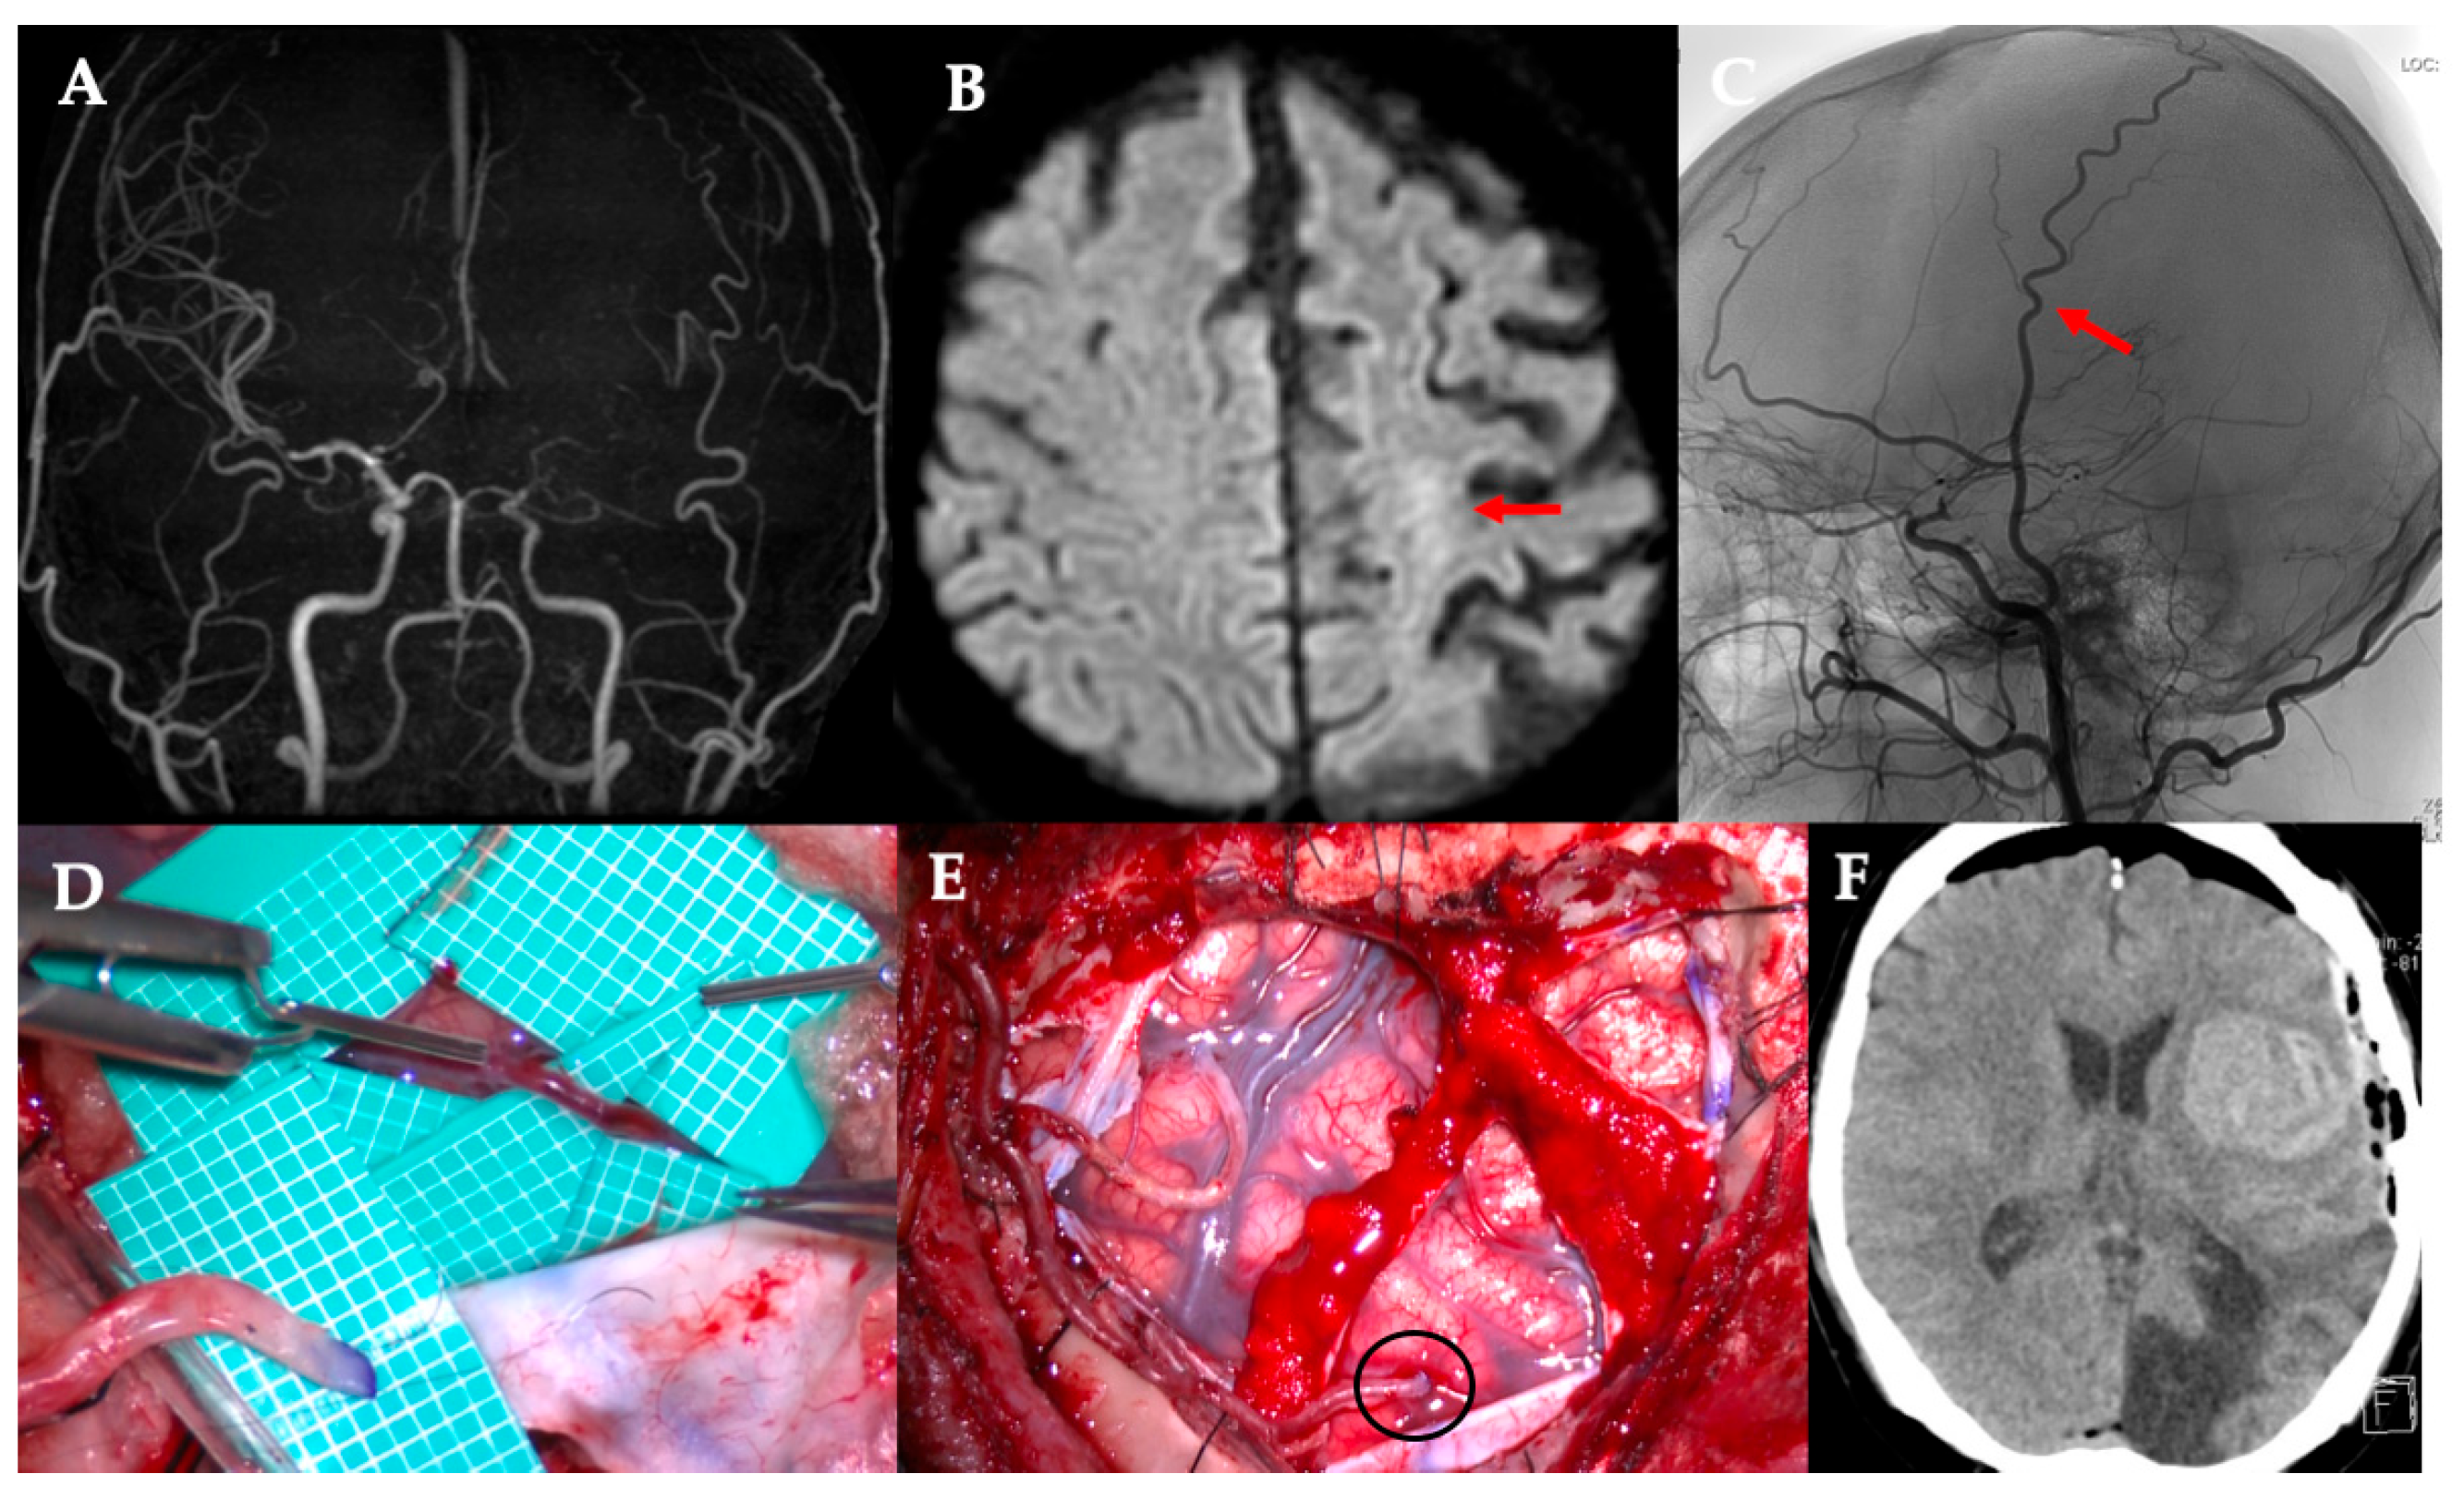

Despite its effectiveness, direct bypass surgery in adult patients with MMD remains challenging. One major concern is that STA donors may not always be optimally suited for anastomosis. The “orthodox” STA-MCA bypass uses one STA branch (frontal or parietal) for a single bypass, or both branches for a double-barrel bypass if broader coverage is needed. However, in some cases, the available cortical recipient artery is very small (diameter < 1 mm), and a larger donor artery can produce a flow surplus and technical difficulty in suturing because of a caliber mismatch. Furthermore, bypass of small recipient vessels is associated with an increased risk of hyperperfusion [3]. Our institutional experience includes cases of cerebral hemorrhage resulting from hyperperfusion following bypass with a significant donor–recipient caliber mismatch (Figure 1). In such situations, conventional bypass using the main STA branch may not be ideal.

Figure 1. Demonstration of a 46-year-old man underwent left-sided revascularization for Moyamoya disease with an ischemic onset. A difference in the caliber was observed between the donor and recipient arteries. The patient was postoperatively managed with sedative intubation due to concerns regarding the risk of hyperperfusion. Immediately after surgery, CT showed extensive cerebral hemorrhage. (A) MRA. Poor delineation of bilateral internal carotid artery endings was observed. (B) DWI. Left acute cerebral infarction was observed (red arrow). (C) STA parietal branch was particularly well developed (red arrow). (D,E) The STA parietal branch trunk (2 mm) was anastomosed to M4 of the frontal lobe (0.9 mm, black circle). (F) Immediately after surgery, extensive cerebral hemorrhage is observed in the left frontal lobe. CT, computed tomography; DWI, diffusion-weighted image; MRA, magnetic resonance angiography; STA, superficial temporal artery.